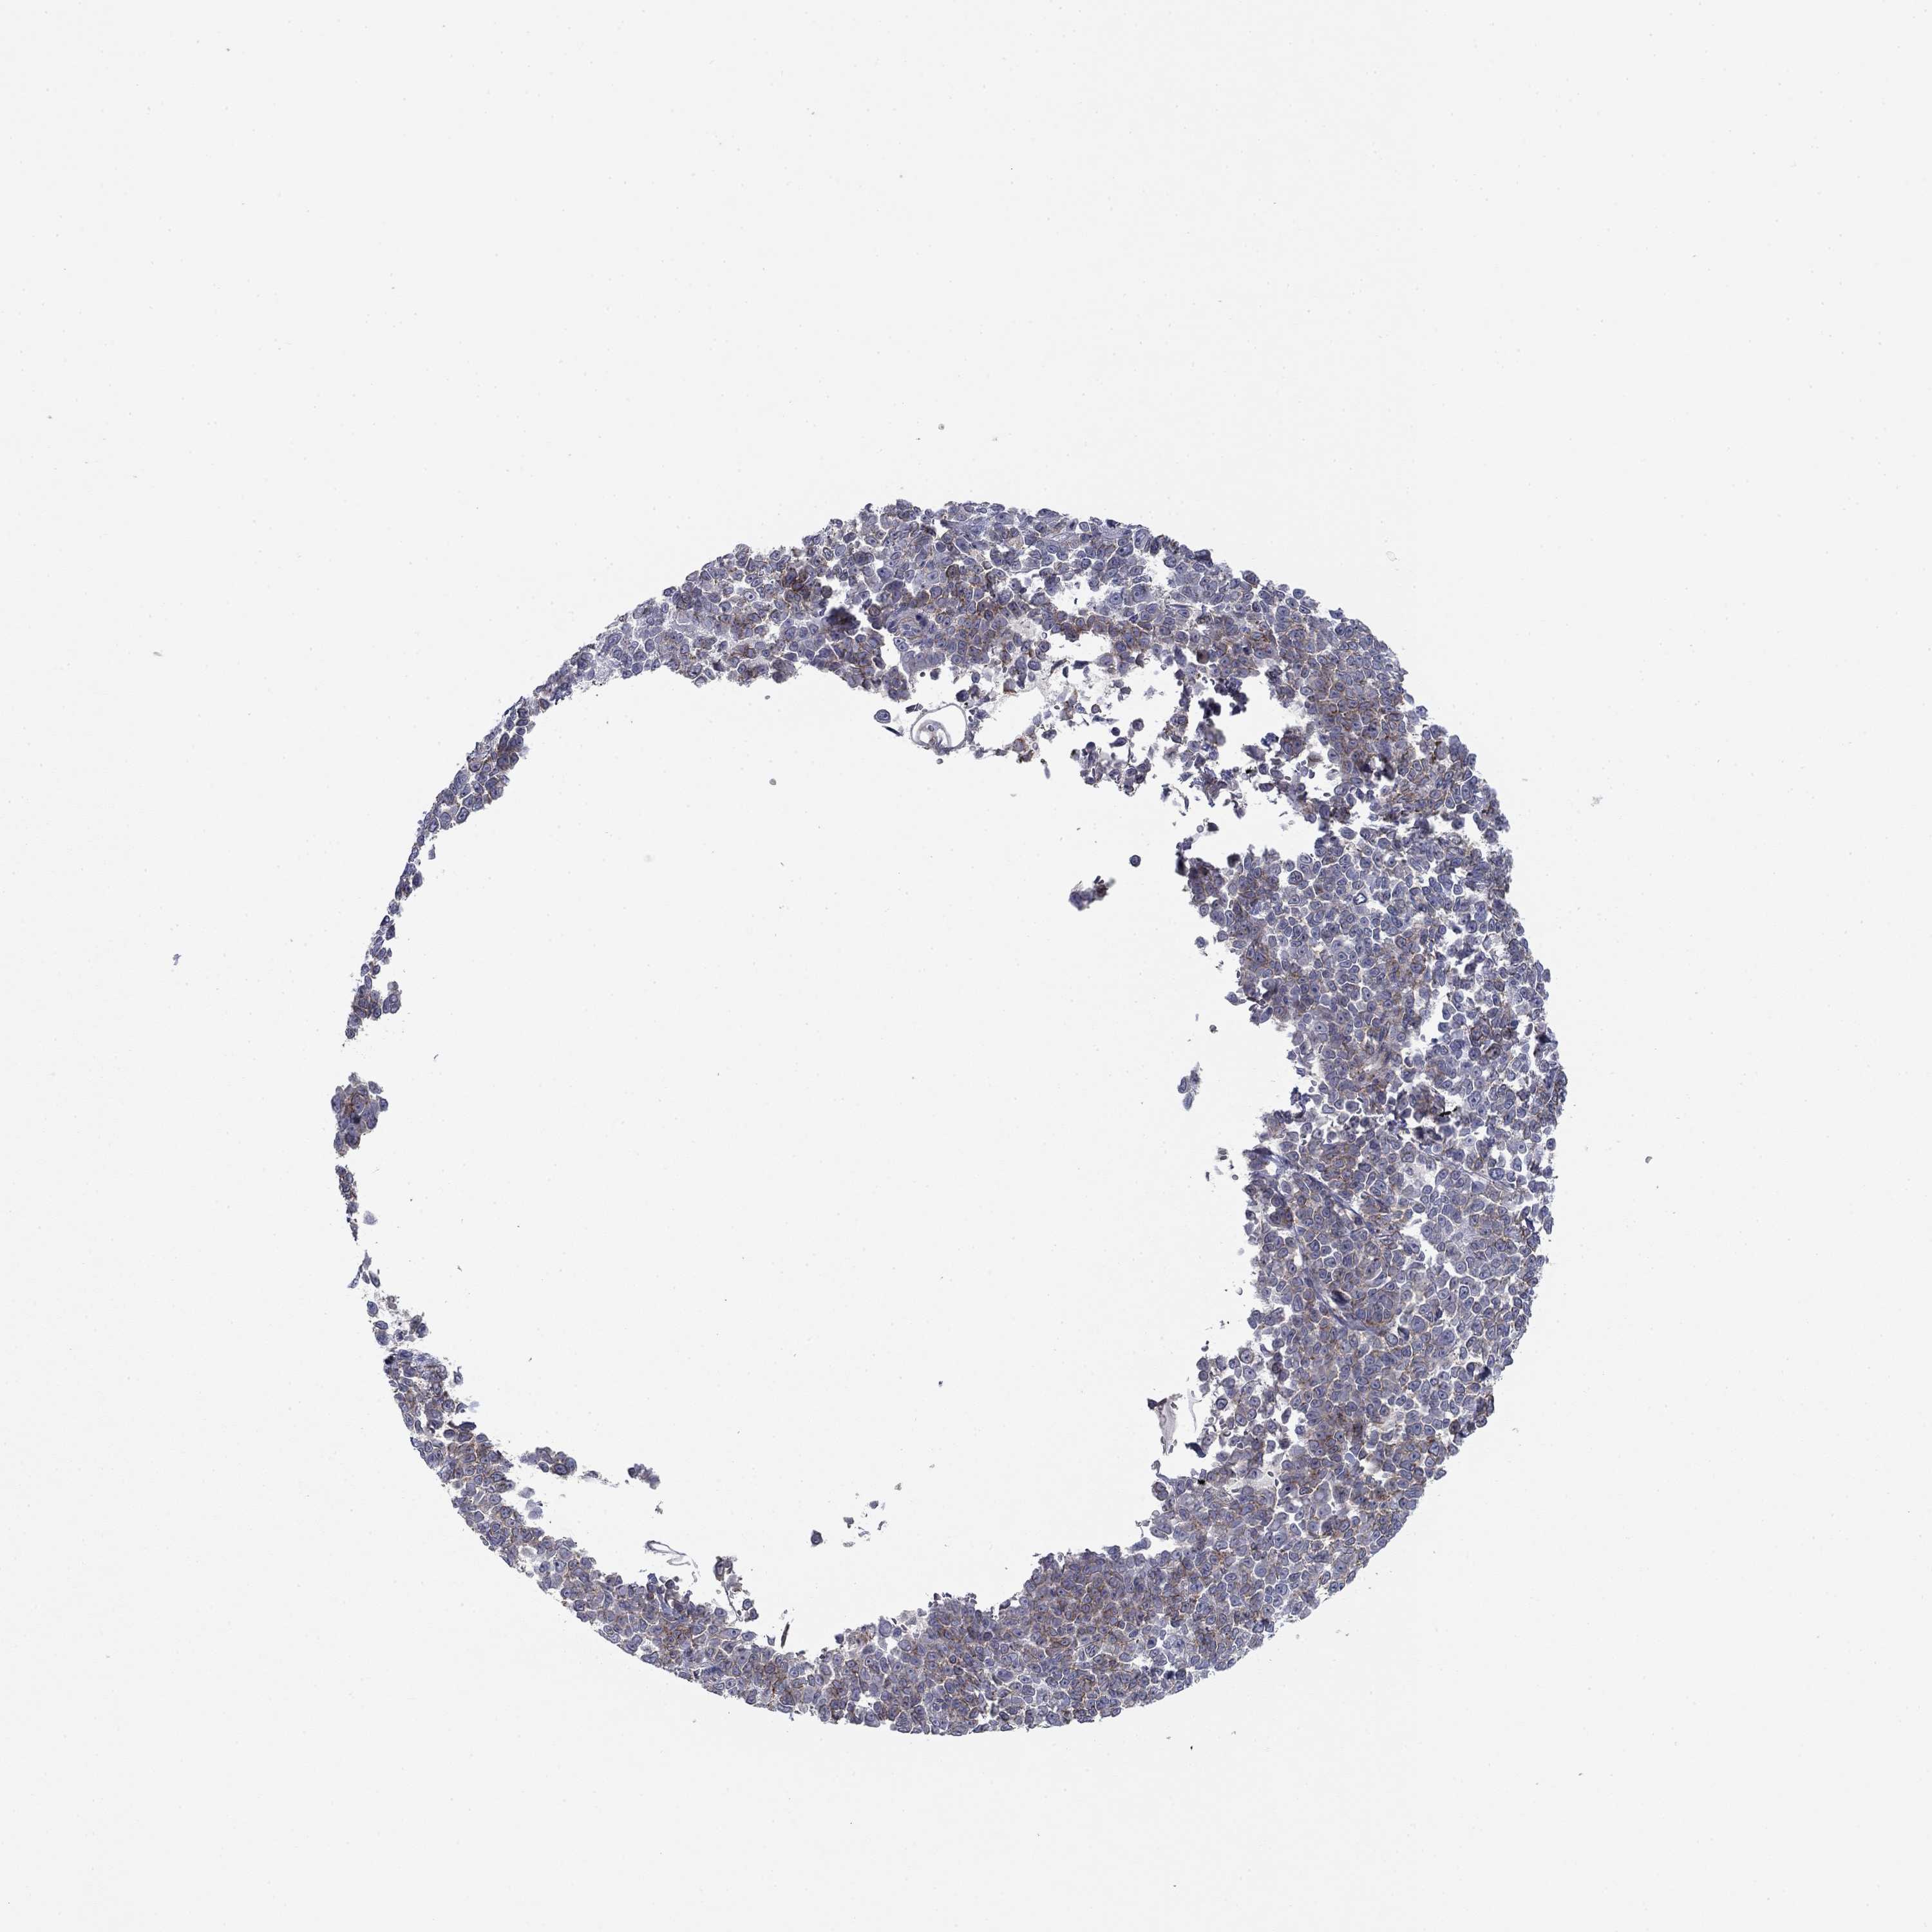

MELANOMA - Protein expressioni

A mouse-over function shows sample information and annotation data. Click on an image to view it in a full screen mode. Samples can be filtered based on level of antibody staining by selecting one or several of the following categories: high, medium, low and not detected. The assay and annotation is described here.

Note that samples used for immunohistochemistry by the Human Protein Atlas do not correspond to samples in the TCGA dataset.

Antibody stainingi

Antibody staining in the annotated cell types in the current human tissue is reported as not detected, low, medium, or high, based on conventional immunohistochemistry profiling in selected tissues. This score is based on the combination of the staining intensity and fraction of stained cells.

Each image is clickable and will lead to virtual microscopy that enables deeper exploration of all samples and also displays staining intensity scores, fraction scores and subcellular localization as well as patient and tissue information for each sample.

Antibody HPA003548

Antibody CAB017633

Staining

High

Medium

Low

Not detected

Intensity

Strong

Moderate

Weak

Negative

Quantity

>75%

75%-25%

<25%

None

Location

Nuclear

Cytoplasmic/membranous

Cytoplasmic/membranous,nuclear

Malignant melanoma, NOS

Malignant melanoma, Metastatic site